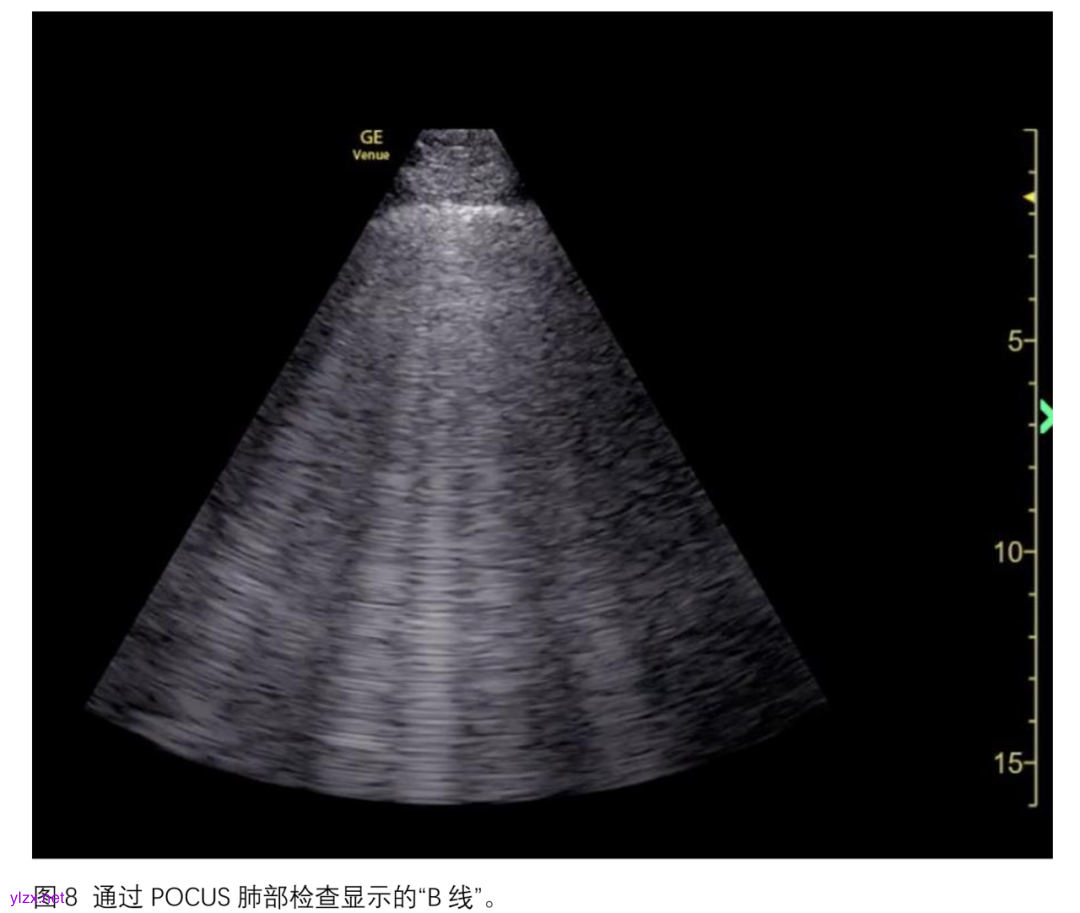

对于肺功能的评估,已有大量研究在特定人群中展开,包括失代偿性心力衰竭、终末期肾病或需要重症监护病房(ICU)收治的患者。肺水肿与肺部评分系统密切相关,通过识别“B线”来评估。B线是由肺泡间隔内液体积聚形成的超声伪像,表现为从胸膜起源并贯穿整个肺实质深度的垂直“B线”(图8)。通常,肺部通气情况根据是否存在B线或肺实变进行区域评分,分数越高表示肺通气越差。将各个肺区域的评分相加,得到综合肺评分。已有研究将肺部通气评分与传统影像学检查(如胸部X光、CT)相关联,用于评估ECMO患者的肺容积状态和肺顺应性改善情况。此外,肺超声评分还与COVID-19患者、新生儿的V-V ECMO撤机成功率以及ECMO支持下ARDS患者的生存率相关。